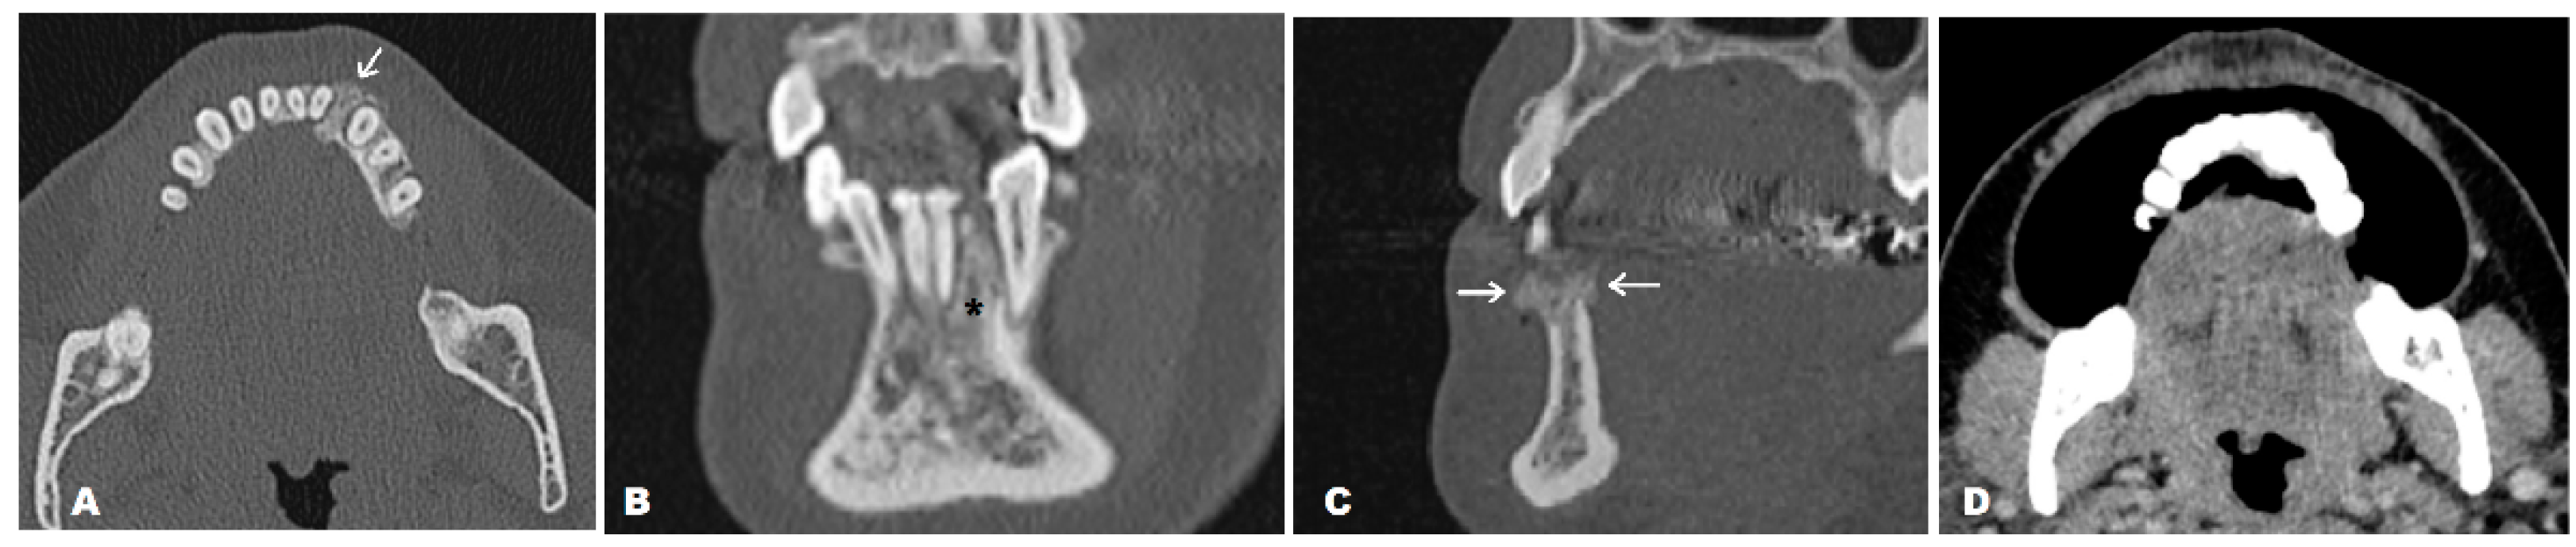

Figure 2. Given the limitations of the CBCT method, a CT scan of the mandible was obtained in both unenhanced and contrast-enhanced (CE) series, primarily in order to evaluate the bone structure of the entire mandible, surrounding soft tissues, and the possible extraoseal propagation of the lesion. A CE scan was performed using the puffed-cheek technique. The lesion was restricted to the alveolar process of the mandible (white arrow) (A), apically slightly exceeding the apexes of the left lower canine and lateral incisor (asterisk) (B). The size of the lesion was 11.6 mm in vestibule–oral diameter, 10.1 mm in lateral diameter, and 14.9 mm in craniocaudal diameter. There were no signs of root resorption – of the affected teeth. Oblique sagittal reconstruction in the bone window confirmed the presence of a periosteal reaction on both cortical plates (white arrows) (C). The CECT showed no enhancement of the adjacent mucosa or surrounding soft tissues (D). After a biopsy, preliminary histopathology reported a neoplasm with chondroid differentiation, mild cellular atypia, and a focus of chondroid tissue calcification but without osteoid deposition, suggesting chondrosarcoma (CS). CS initially suspected to be a periodontal lesion is atypical and rare. To the best of our knowledge, only six similar cases have been reported so far [1,3,4,5,6]. The absence of a typical lytic growth pattern and visible calcifications in this case could be explained by the relatively small size of the tumor, approximately 1 centimeter in the greatest diameter. The irregularity of the borders primarily implied protrusive growth but without extension into the nearby structures.